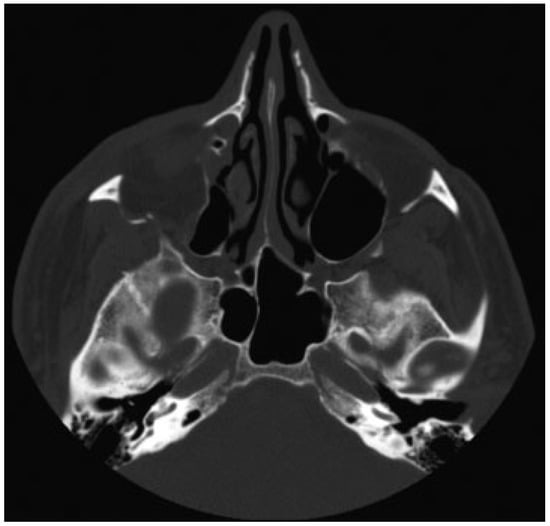

The authors defined simple LOWF as any fracture consisting of two boney pieces (Figure 1) and comminuted fractures as any fracture consisting of three or more pieces (Figure 2). Only patients who sustained fractures through primary trauma were included in this study. This excluded patients whose fractures were due to tumor resection or patients with a history of previous fractures of the lateral orbit. The senior investigator (W.S.) of this study identified the presence of all fractures, which were also confirmed upon review of the official radiology report.

Figure 2.

Comminuted lateral orbital wall fracture.